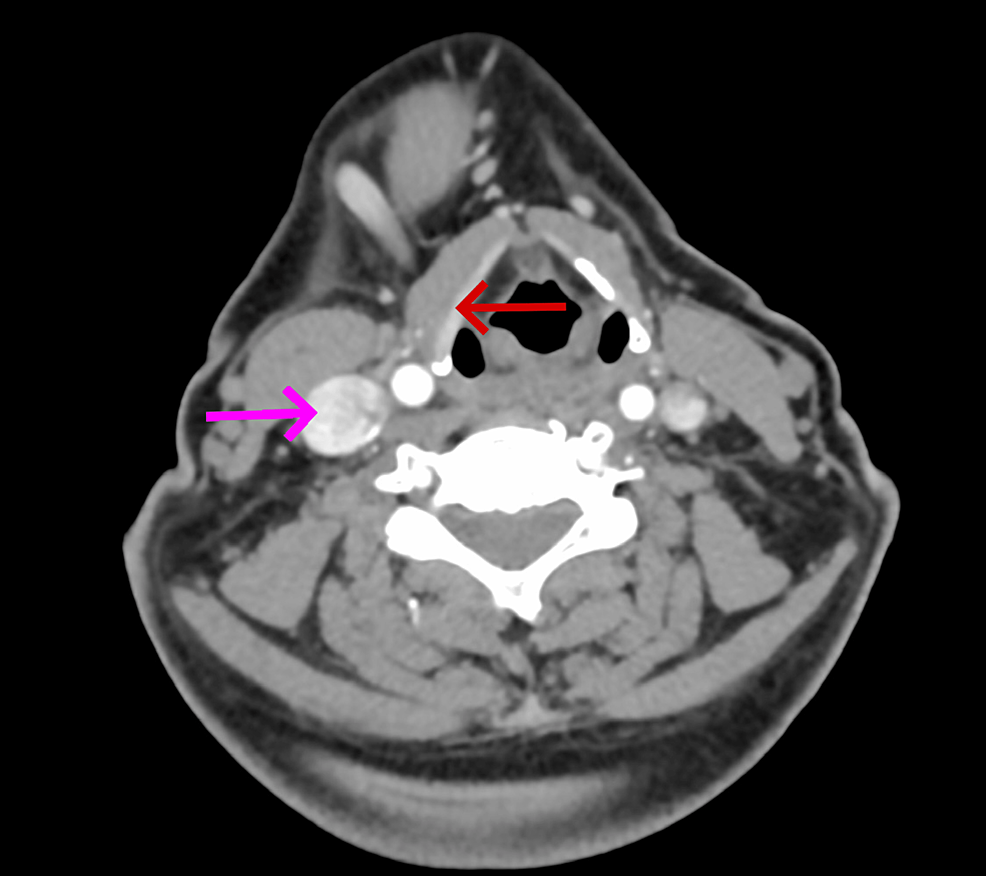

On local examination, there was a single firm mobile swelling in the right submandibular region measuring 5*4 cm and was non-tender. All relevant investigations were done and had normal thyroid function studies. Ultrasonography of the right submandibular region showed an enlarged submandibular gland with a hypoechoic lesion and vascularity on Doppler, suggestive of submandibular sialadenitis (Figure 1). FNAC of the swelling was done, and it showed numerous small basaloid cells in singles and multilayered. These cells have round to regular/oval nuclei with bland, granular chromatin. The background shows a few naked nuclei with fibrous scanty chondromyxoid stroma and hyaline material. These features are suggestive of a basaloid neoplasm like basal cell adenoma or pleomorphic adenoma. Contrast-enhanced computed tomography (CECT) of the neck showed a large lobulated mass with irregular margins and cystic areas in the right submandibular region extending up to the midline; post-contrast showed heterogenous enhancement with necrosis and coarse calcific foci within the lesion, suggestive of malignant neoplasm such as adenoid cystic carcinoma with origin from the deep lobe of the submandibular gland (Figure 2). Another small enhancing lesion with coarse calcific foci was seen at the left pharyngeal mucosal space, suggestive of a metastatic lingual lymph node. Also, the thyroid gland was not visualized, and a small oval isodense lesion with homogenous post-contrast enhancement was seen in the left lateral aspect of trachea, in the expected location of thyroid, suggestive of remnant thyroid/congenital hypoplastic thyroid. Thus the patient was advised surgical excision of the swelling.